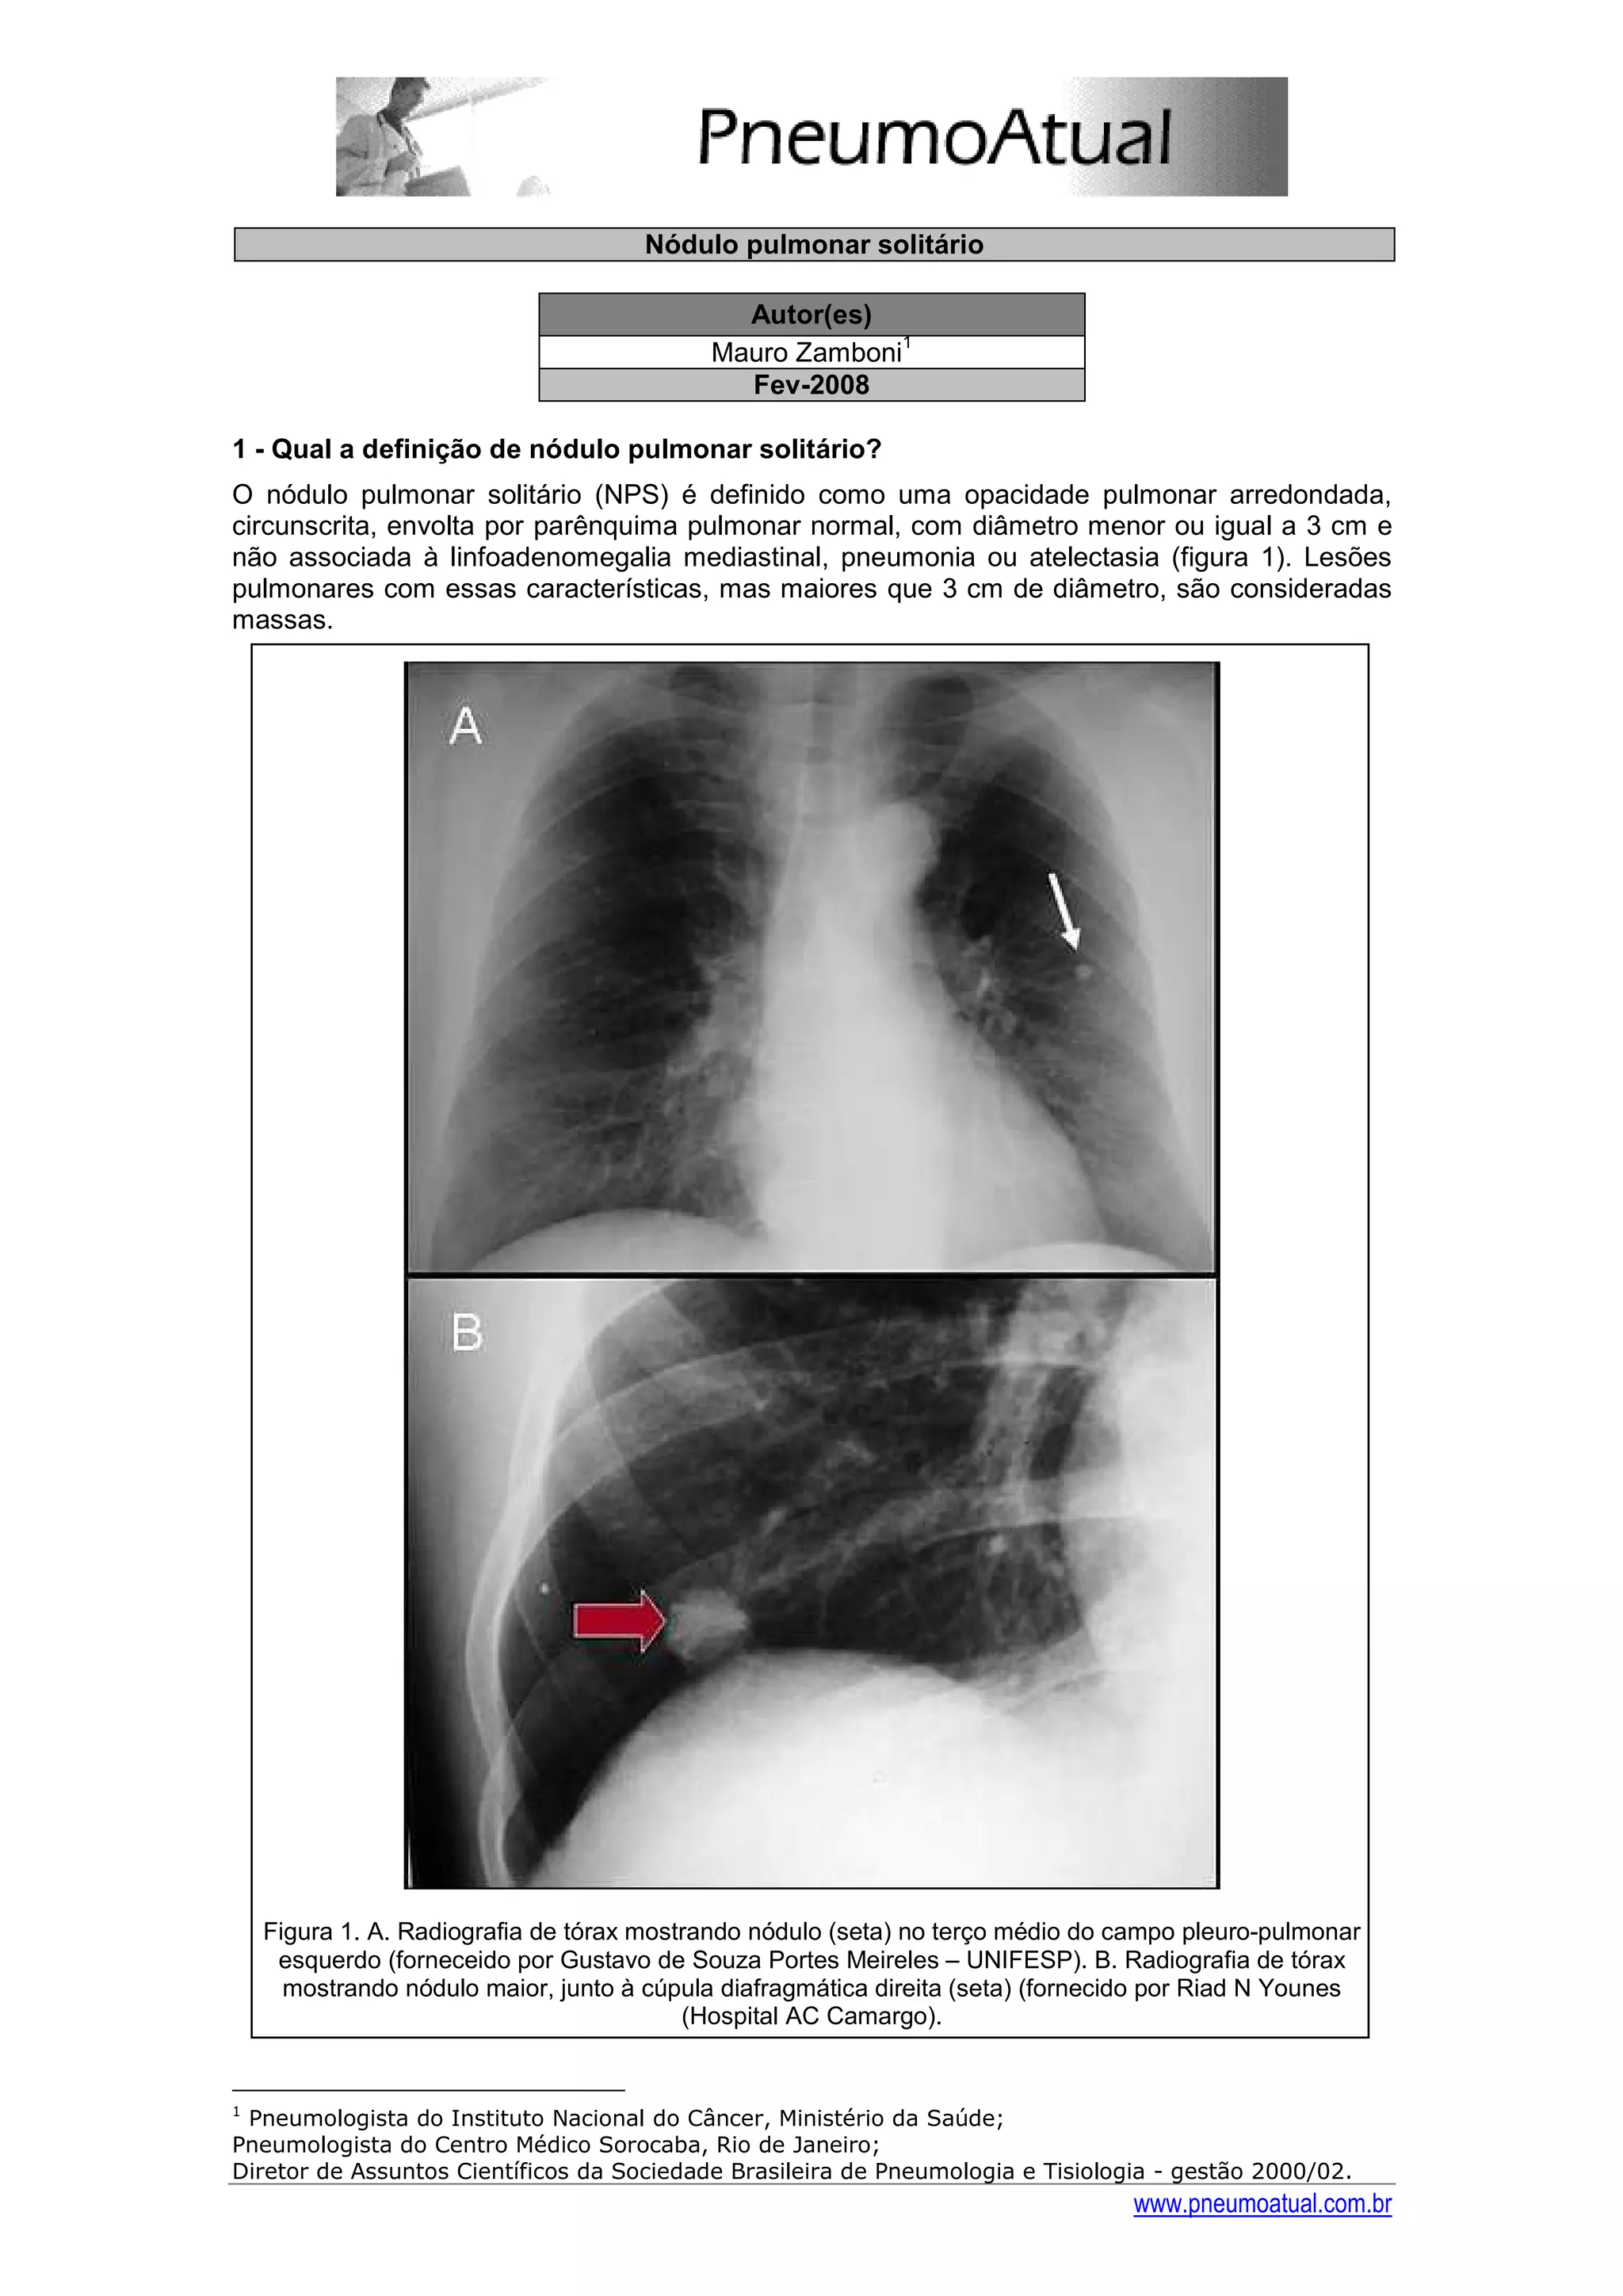

O nódulo pulmonar solitário (NPS) é definido como uma opacidade pulmonar arredondada,

circunscrita, envolta por parênquima pulmonar normal, com diâmetro menor ou igual a 3 cm e

não associada à linfoadenomegalia mediastinal, pneumonia ou atelectasia (figura 1). Lesões

pulmonares com essas características, mas maiores que 3 cm de diâmetro, são consideradas

massas.

Figura 1. A. Radiografia de tórax mostrando nódulo (seta) no terço médio do campo pleuro-pulmonar

esquerdo (forneceido por Gustavo de Souza Portes Meireles – UNIFESP). B. Radiografia de tórax

mostrando nódulo maior, junto à cúpula diafragmática direita (seta) (fornecido por Riad N Younes

(Hospital AC Camargo).